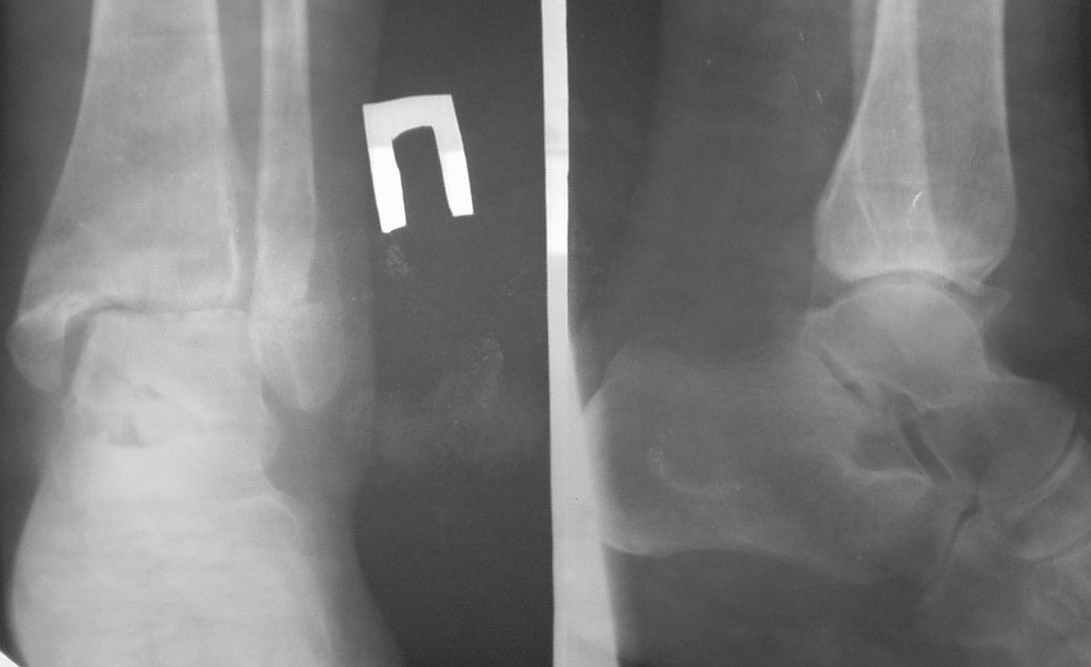

На консультацию пришла больная 39 лет, перелом лодыжек 8 месяцев назад. Лечилась консервативно в одном из стационаров области.

Сейчас беспокоят постоянный болевой синдром и отек, затрудняющий ношение стандартной обуви. На КТ - межберцовый синдесмоз 4,5 мм (на здоровой ноге - 2,0 мм). Деформирующие краевые костные разрастания по внутренней замыкательной пластине мало-, большеберцовой и таранной костей.